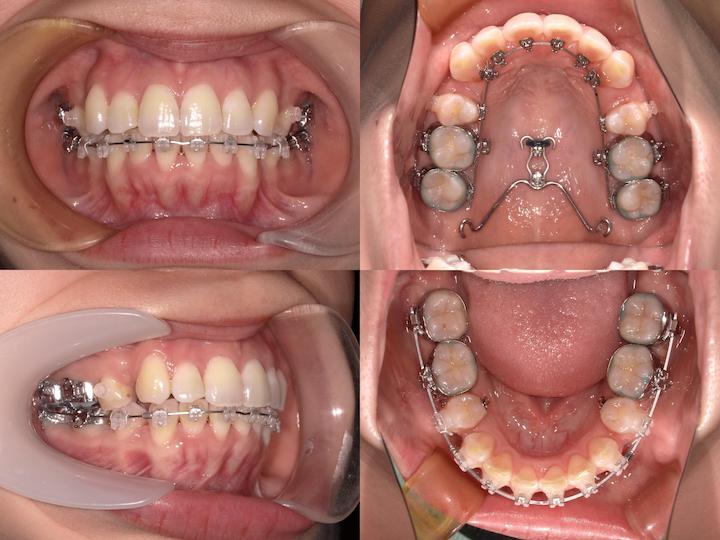

上顎は裏側矯正で、下顎は表側矯正で治療しました。

この症例ではアンカースクリューはPLAS(パラタルレバーアームシステム)を使用しています。

さらに、前歯の後方移動時に奥歯が前方に移動しないよう、正中口蓋縫合部にPLAS(パラタルレバーアームシステム)を植立し、大臼歯を固定しています。

上顎は裏側矯正、下顎は表側矯正装置のハーフリンガルで対応しました。